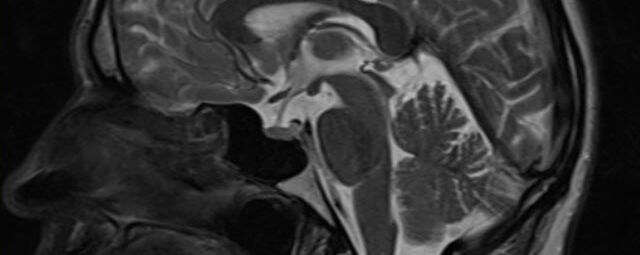

Im Magnetresonanztomographen liegt die zu untersuchende Person in einem starken, homogenen Magnetfeld. Dieses Magnetfeld bewirkt eine gemeinsame Ausrichtung der Wasserstoffprotonen im Körper entlang der Längsachse des Magnetfeldes. Wird nun diesen Teilchen Energie in Form von Radiowellen in einer genau abgegrenzten Frequenz zugeführt, so werden sie aus ihrer ursprünglichen Orientierung abgelenkt.

Die zugeführte Energie wird in gewebespezifischer Weise wieder abgegeben. Ein hochempfindliches Computersystem misst die unterschiedliche Energieabgabe und setzt sie in Bildinformationen um. Jede Körperregion kann somit durch Schnittbilder in allen Raumebenen oder durch dreidimensionale Rekonstruktionen mit einem exzellenten Weichteilkontrast dargestellt werden. Es besteht keine Belastung durch Röntgenstrahlen.

Kopf/Hals

Kopf

• akute Schlaganfalldiagnostik und chronische Durchblutungsstörungen

• entzündliche Prozesse des Gehirns oder der Gesichtsweichteile

• Tumore, ggf. mit Spektroskopie

• Abklärung Schwindel, zentrale Sehstörung, Kopfschmerz

• Metastasenverdacht

• Multiple Sklerose

• Abklärung Hirnnerven, Schädelbasis inkl. Hypophyse

• Abklärung Kleinhirn, Hirnstamm, Halsmark